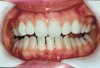

Figure 8  Prior to at-home whitening. Following approximately 10 days of at-home tray whitening.

Figure 9  Prior to at-home whitening. Following approximately 10 days of at-home tray whitening.